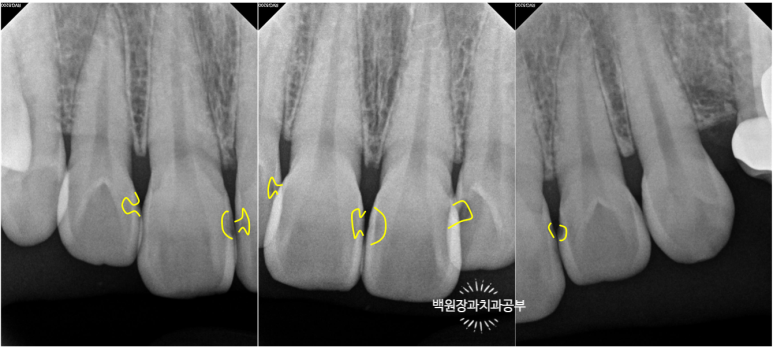

총 세장의 치과용 치근단 방사선사진을 찍었고,

각 치아마다 옆면의 충치 범위를 확인할 수 있었어요!

까맣게 물들듯 보이는 곳들이 충기가 있는 곳입니다.

치과용 엑스레이 판독을 일반 사람이 하기는 힘드니깐,

제가 보기 쉽게 표시해 드릴께요!!

노란색으로 표시해 놓은 곳들이 옆면 충치가 있는 곳들이에요!

눈으로 확인하는 시진과 방사선 검사를 종합해서 합집합이 되는 부위를 모두 치료하면 됩니다.